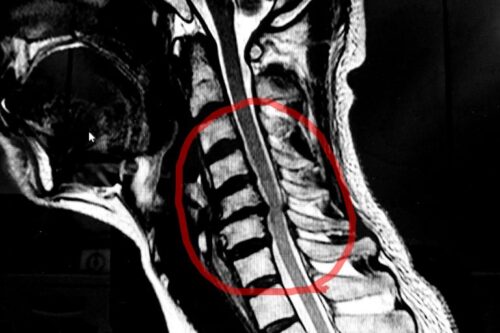

【症例】頚椎症と診断を受けた50代男性、左肩から指先まで続いていた痺れが改善したケース